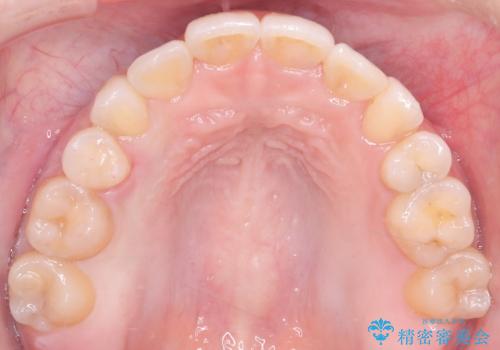

インビザラインによる精密な仕上げ: 全体のがたつきが概ね整った段階で、インビザライン(マウスピース矯正)へ移行しました。透明で目立たないマウスピースを使用しながら、0.1mm単位の細かな歯の配置や、最終的な咬み合わせのバランスを精密に整えていきました。

治療の結果、重度のがたつきは跡形もなく解消され、抜歯したスペースもきれいに閉じました。ワイヤーによる「確実な移動」と、インビザラインによる「緻密な仕上げ」を組み合わせることで、審美性と機能性の両立を叶えた美しい歯並びを実現しました。